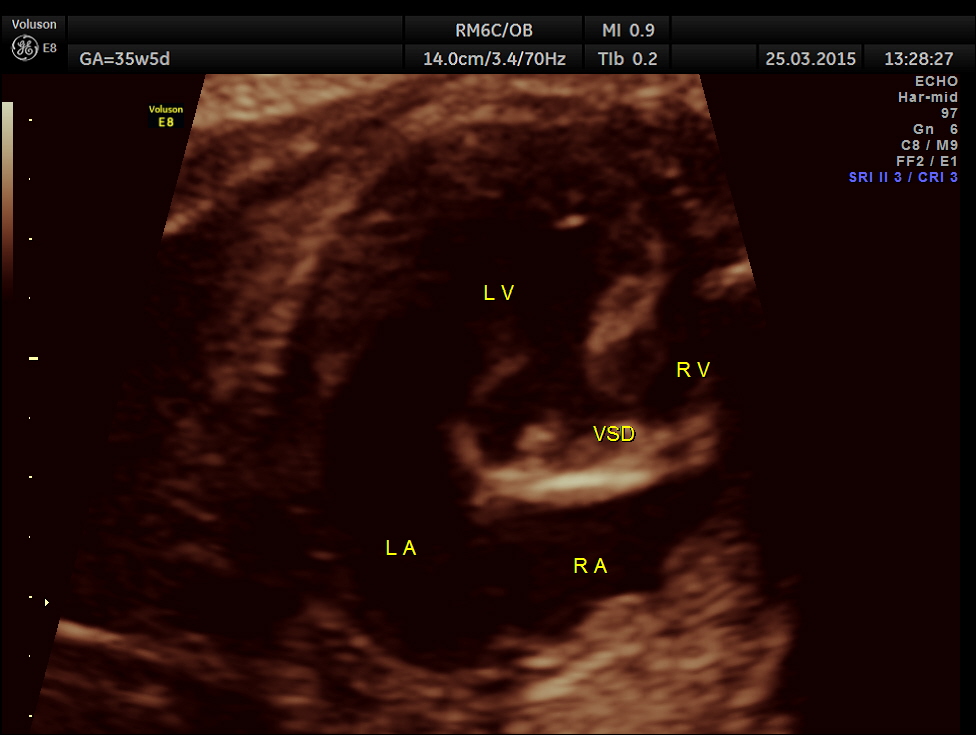

Cardiomegaly with dilated left ventricle and small right ventricle were obvious.

Ventricular Septal Defect is seen.

The 4 chamber view showed LV to be dilated.

Ventricular Septal Defect is seen .